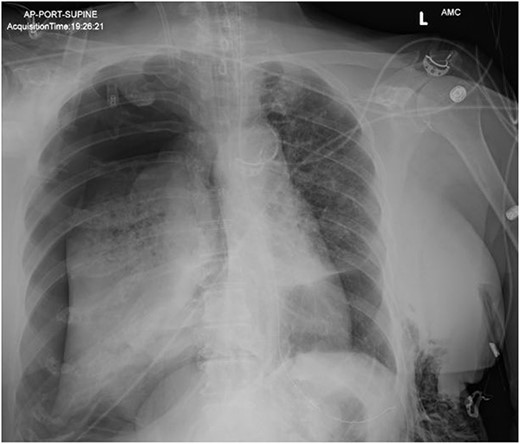

In the operating room (OR), the patient underwent intubation for TBNA using the Monarch® robotic bronchoscopy platform. Nine needle aspirations were obtained from the third-order RLL bronchi with each aliquot subjected to rapid on-site examination. While awaiting results, the patient developed retching, hemoptysis, bronchial bleeding from the superior segment of the RLL lobe and hypotension. The bleeding was managed with ice-cold saline and epinephrine. The patient required aggressive resuscitation with crystalloid, blood products and vasopressor therapy. She was transferred to the ICU where she remained intubated for ongoing resuscitation. In the ICU, the patient developed recurrent hypotension. Chest X-ray (CXR) revealed a right-sided pneumothorax (Fig. 1) that was treated with a small-bore pigtail chest tube and resulted in immediate improvement of her tension physiology. The pneumothorax resolved on repeat chest film while the patient remained intubated and sedated (Fig. 2).